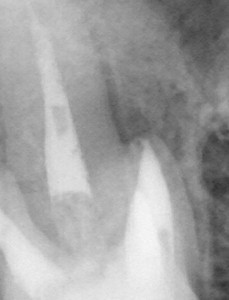

こないだ、話題にあげた、ゆーくり治るケースも多いですが、治癒が早くてびっくりすることも多いです。

MB根に大きい病巣があります。

アンダー+MB2が未処置というのが原因かと考え、

たまたま仮歯が外れて来院してくれたんでついでにレントゲン撮らせてもらうと

想像してたより治癒が早くて驚きました。

こんな感じで、症例によってほんと、治癒のスピードはまちまち。

予測不能です。